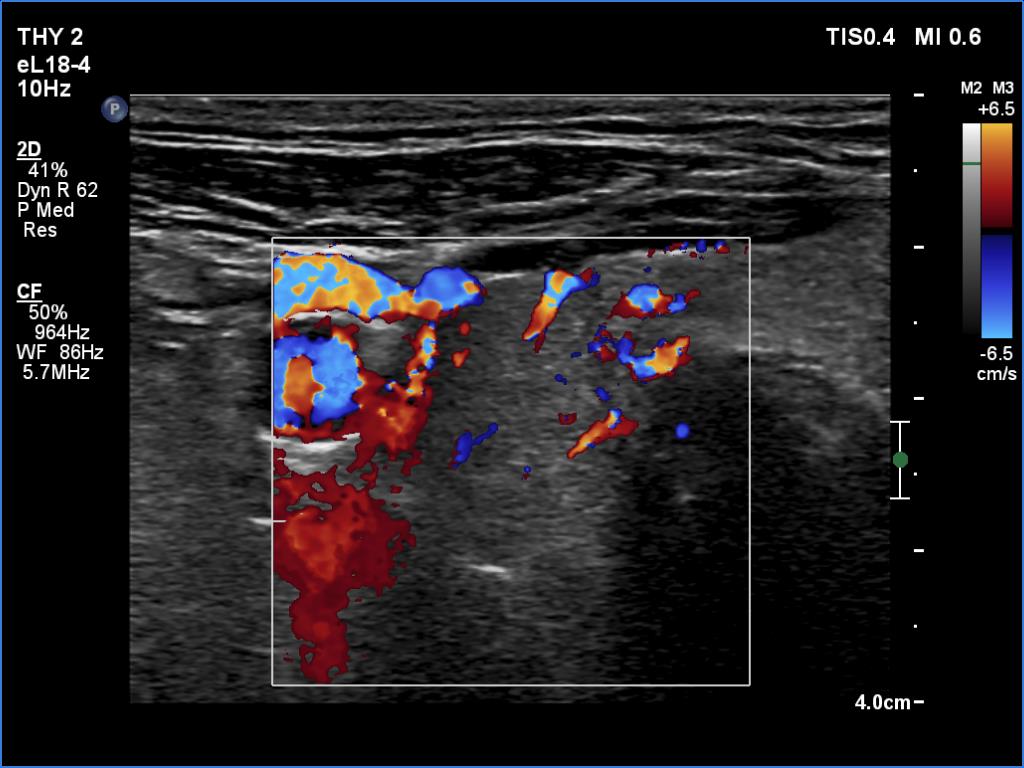

Ultrasonography. The right lobe was echonormal and intact. A large mass occupied almost the entire left lobe. On this side, normal thyroid tissue could only be identified in the dorsal part. The mass was composed of echonormal and hypoechoic areas, had macrocalcifications, irregular intranodular vascularity and proved to be very hard on elastography. There were multiple lymph nodes in III, IV and V left neck compartments. One of the nodes was in close proximity to the jugular vein and was suspicious of having broken into the vessel. The trachea was significantly narrowed at the lower level of the thyroid.

US-guided aspiration was performed from the thyroid mass and from the lymph node presented in the images. Cytology resulted in all three cases in metastatic carcinoma. Wash out thyroglobulin levels were 2.02 and 8.19 ng/L in the thyroid mass and in the neck lymph node, respectively.

2. There are several remarkable findings in this case, e.g., the destruction of the left lobe by the tumor, the elastography pattern, the relation of the largest metastatic lymph node and the jugular vein, the ultrasound demonstration of the trachea' stricture.